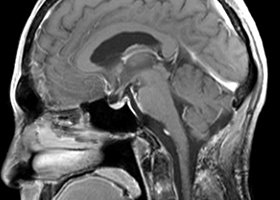

③ もやもや病に対する頭蓋内外脳血行再建術

もやもや病は原因不明の進行性脳内血管狭窄疾患であり、国によって難病指定されている病気です。典型的には小児や若年成人に起こり、脳虚血(脳梗塞)、脳出血を生じます。頭蓋内外脳血行再建術(バイパス手術)が必要な場合があります。

38歳、もやもや病、左半身一過性脳虚血発作

[画像所見]

-

右 頭部MRI -

頭部MRA(脳血管の脱落、赤丸部) 左